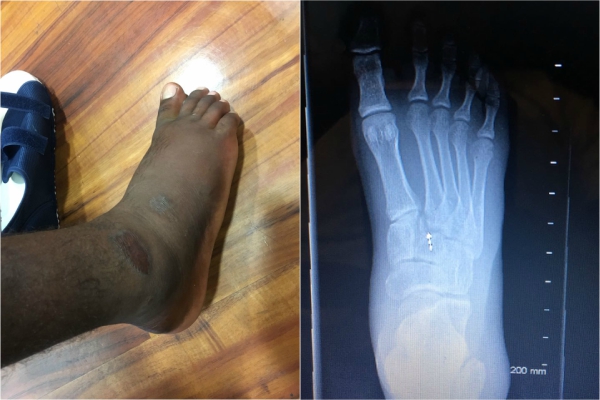

O resgate do capixaba foi feito por colegas e também por uma equipe que fazia a segurança dos praticantes. Lucas Medeiros, de 24 anos, foi encaminhado para um hospital da região, onde lhe foi diagnosticado uma grave fratura no pé direito, que quebrou em três partes.

Lesão no pé direito de Lucas Medeiros Crédito: Acervo Pessoal

“Existe fratura na base do segundo metatarson e também tem fratura na base do quarto metatarson. E uma lesão na articulação. O critério é instabilidade mecânica, pois olhei algumas fotos e o ligamento lisfranc foi quebrado. Isso faz com que o atleta venha sentir dor. Agora é ver o grau dessa lesão com mais calma para saber o critério que precisará ser feito para fixar a região. Mas, antes de afirmar qualquer coisa, uma radiografia do pé esquerdo precisará ser feita para que eu possa comparar os dois pés. Pode ser que exista a necessidade de fazer uma cirurgia no local”, explicou o ortopedista.